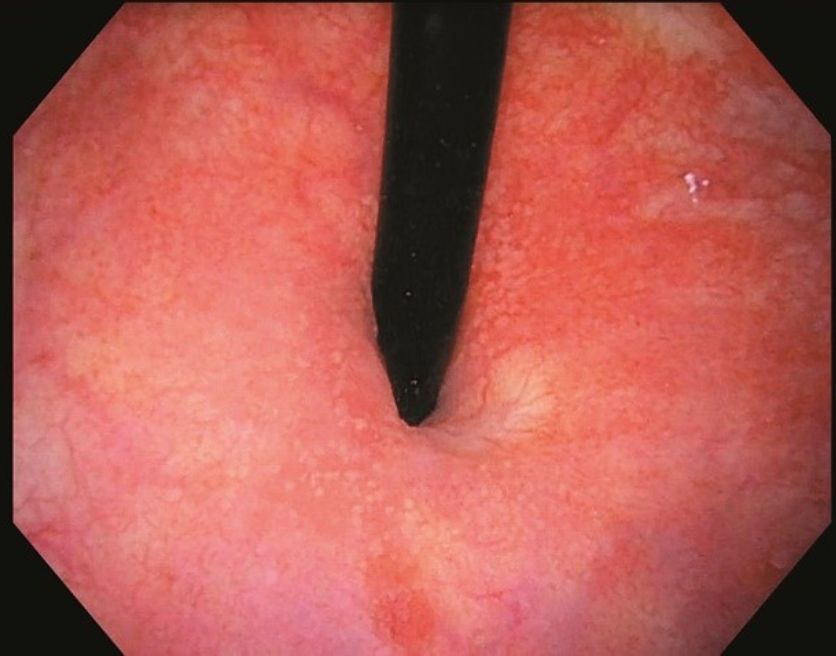

A visão clara na uretra melhora a detecção e o diagnóstico de áreas suspeitas. Sob luz branca, o CYF-VH permite uma visão ampla e detalhada, o que é necessário para cistoscopias de acompanhamento de câncer de bexiga.

Evolution Tip™: Permite fácil navegação e pode proporcionar conforto ao paciente.

Deflexão: O CYF-VH permite um ângulo de deflexão de 220° para cima e 130° para baixo, proporcionando a capacidade de ver e tratar áreas da bexiga.

Grande campo de visão: O amplo campo de visão de 120° oferece uma visualização panorâmica de toda a bexiga a partir do colo vesical.